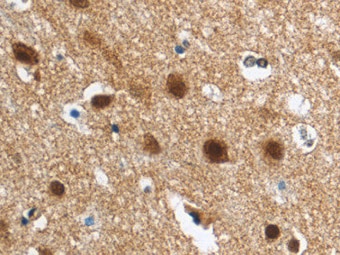

Neurogranin in Human Brain (Cortex). Neurogranin was detected in immersion fixed paraffin-embedded sections of human brain (cortex) using Mouse Anti-Human Neurogranin Monoclonal Antibody (Catalog # MAB79471) at 5 µg/mL for 1 hour at room temperature followed by incubation with the Anti-Mouse IgG VisUCyte™ HRP Polymer Antibody (Catalog # VC001). Before incubation with the primary antibody, tissue was subjected to heat-induced epitope retrieval using Antigen Retrieval Reagent-Basic (Catalog # CTS013). Tissue was stained using DAB (brown) and counterstained with hematoxylin (blue). Specific staining was localized to cytoplasm in neurons. View our protocol for IHC Staining with VisUCyte HRP Polymer Detection Reagents.